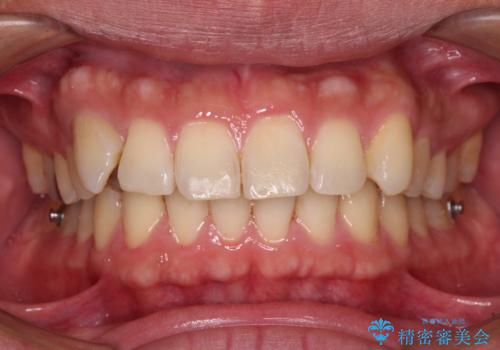

- 前歯のデコボコを気にして来院された患者様です。

当院でインビザライン矯正治療をされている方からのご紹介ということで、インビザラインでの矯正治療をご希望でした。

ワイヤー矯正に比べ来院頻度は低いものの、新幹線での通院のため、やや治療期間が延びることが懸念されました。